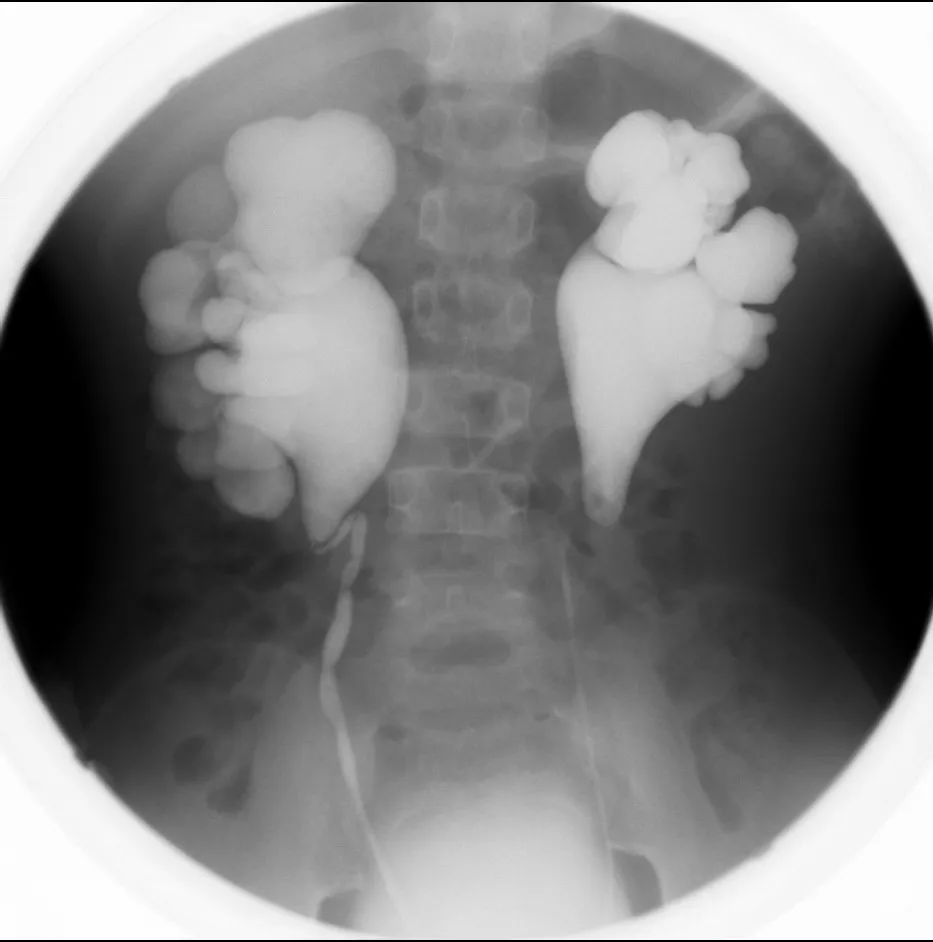

肾盂输尿管重复畸形

胚胎早期有两个输尿管芽进入一个后肾胚基所致。

一个肾脏分为上、下两部,各有一套肾盂和输尿管。上、下两部多不相等,上部肾盂往往细小,发育不全,下肾盂较大。

尿路造影是诊断肾盂输尿管重复畸形的首选方法